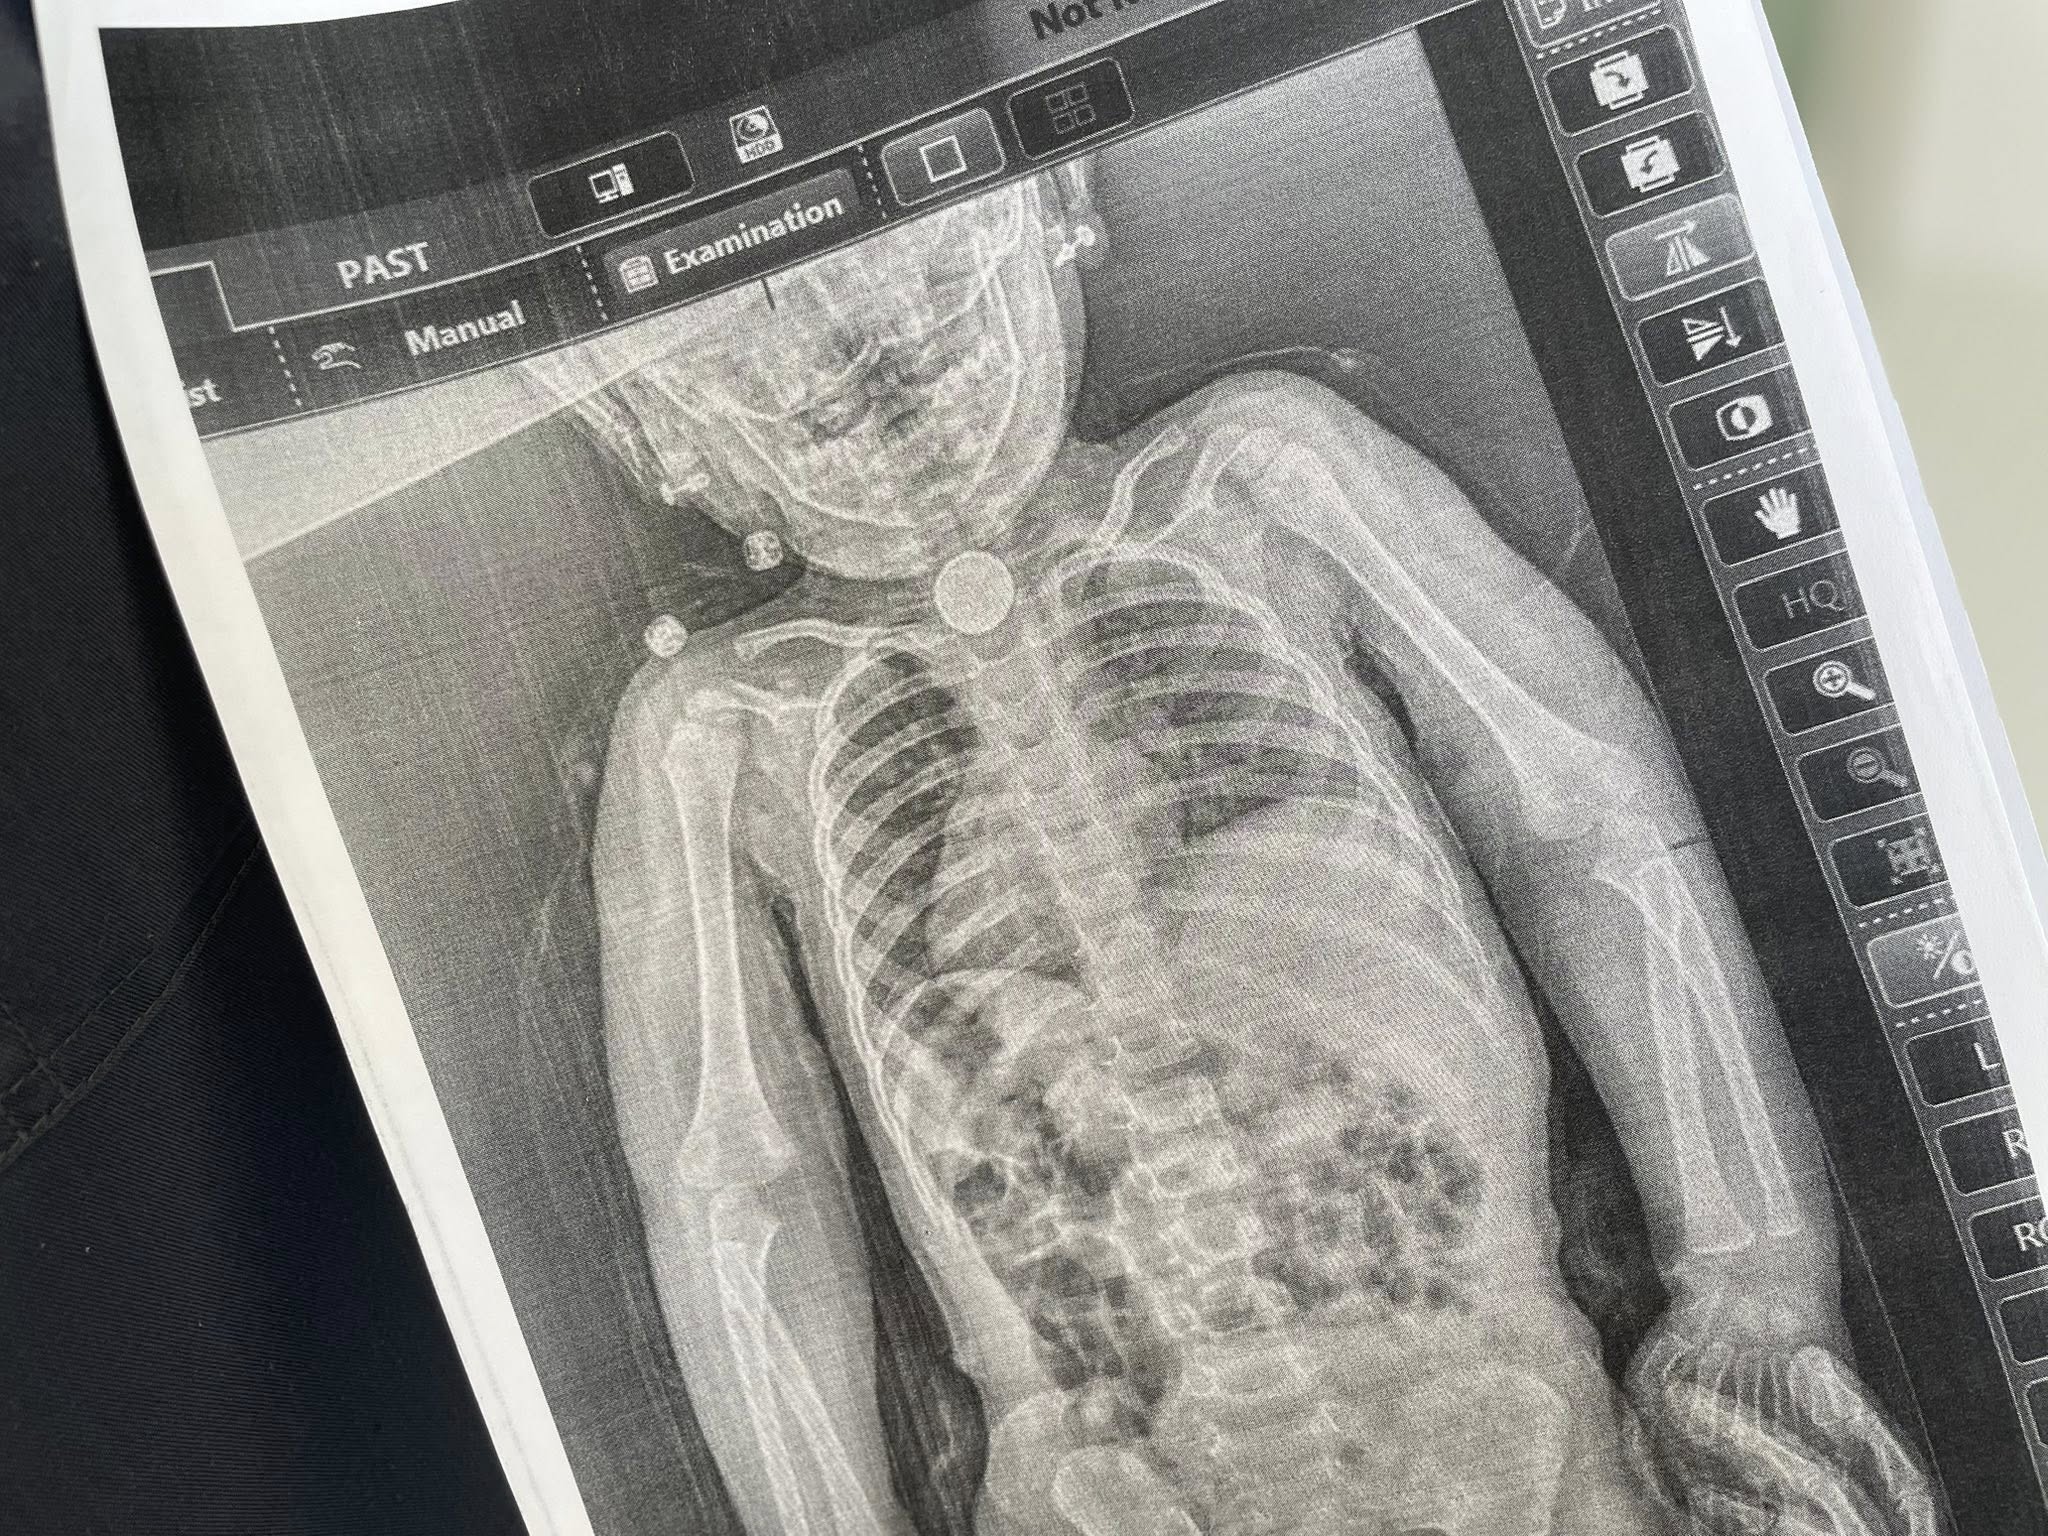

У стравоході дитини застрягла кругла літієва батарейка

Під час ендоскопії лікарі встановили, що у стравоході застрягла кругла літієва батарейка діаметром близько 2,5 см. Навколо неї вже сформувалися набряк і почалося ушкодження слизової.